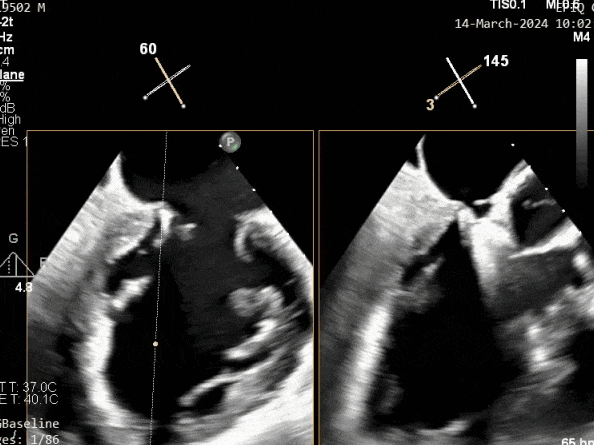

超声心动图:

二尖瓣后叶活动受限,呈房源性栓系,以P3区为重,二尖瓣前叶假性脱垂,二尖瓣瓣环前后径49mm,左右径40mm。

PISA法测r=12mm,EROA=0.72cm2,RVOL=100ml,RF 26%。LVEDD 57mm,左房71*59*77mm,右房55*69mm,LVEF 70%。

超声提示:

二尖瓣反流(重度,4+级,Carpentier I型)

三尖瓣反流(轻度)

主动脉瓣反流(轻度)

双房及心耳内未见确切血栓回声